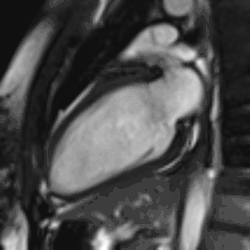

Rather, it is typically used in concert with other diagnostic techniques. In general, the clinical reasons for a CMR examination fall into one or more of the following categories: (1) when echocardiography (cardiac ultrasound) cannot provide sufficient diagnostic information, (2) as an alternative to diagnostic cardiac catheterization which involve risks including x-ray radiation exposure, (3) to obtain diagnostic information for which CMR offers unique advantages such as blood flow measurement or identification of cardiac masses, and (4) when clinical assessment and other diagnostic tests are inconsistent. Examples of conditions in which CMR is often used include tetralogy of Fallot, transposition of the great arteries, coarctation of the aorta, single ventricle heart disease, abnormalities of the pulmonary veins, atrial septal defect, connective tissue diseases such as Marfan syndrome, vascular rings, abnormal origins of the coronary arteries, and cardiac tumors.

Atrial septal defect with dilation of the right ventricle by CMR